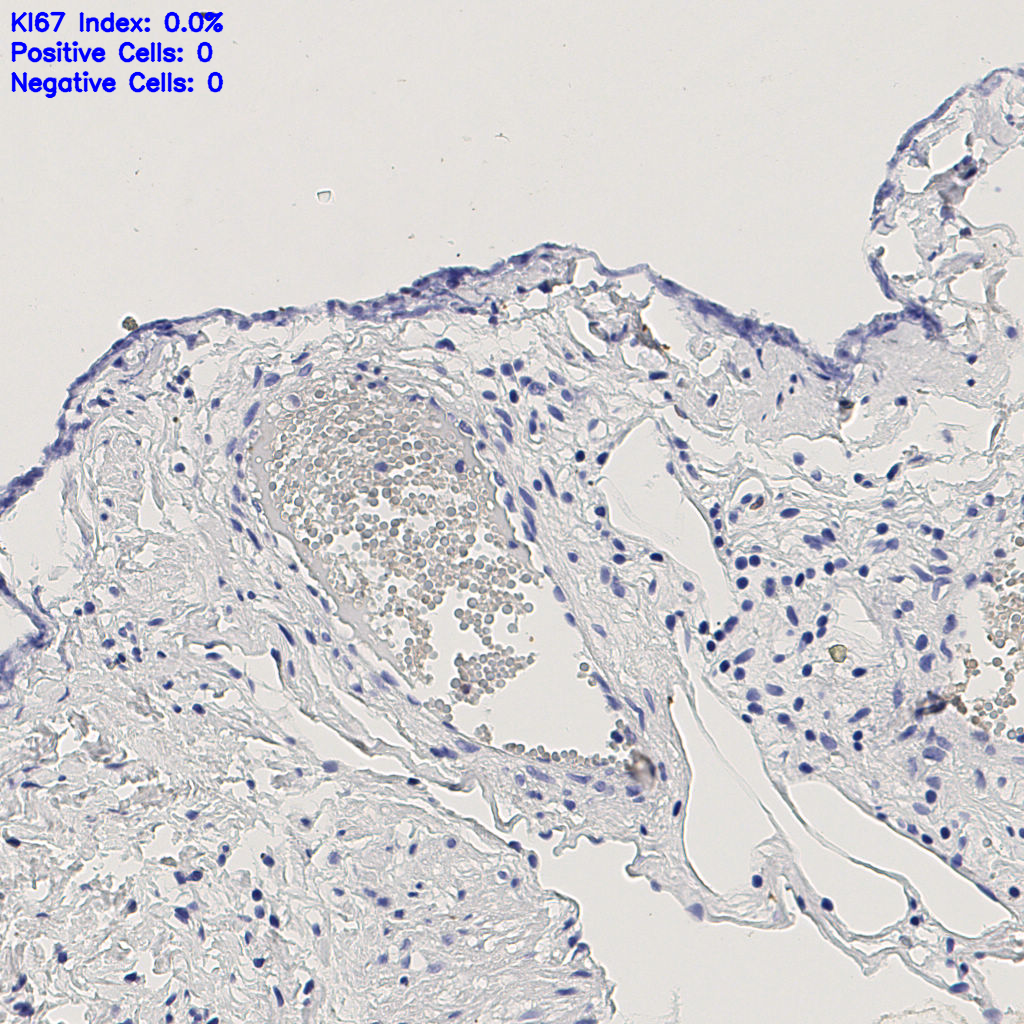

标记后

标记前